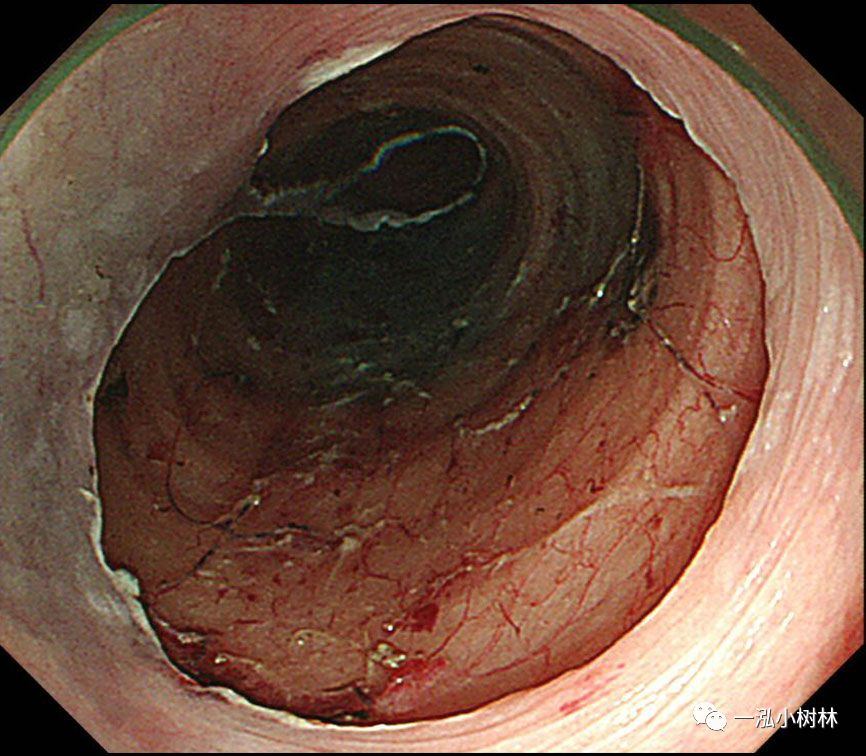

图11 黏膜整块切除